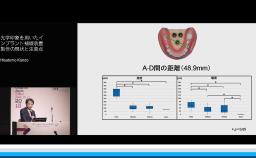

本講演では,上顎洞底挙上術の一手法である側方開窓術の術前臨床的判断基準,術式詳細,臨床経過,CBCT所見,術後偶発症,文献的考察から,開窓部へのバリアメンブレン設置を整理する.

上顎洞の解剖が理解できる。

上顎洞底挙上術(術式や合併症など)の理論が理解できる。